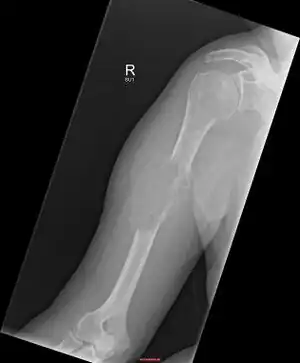

Micrograph of a plasmacytoma. -

Micrograph of a plasmacytoma. H&E stain.